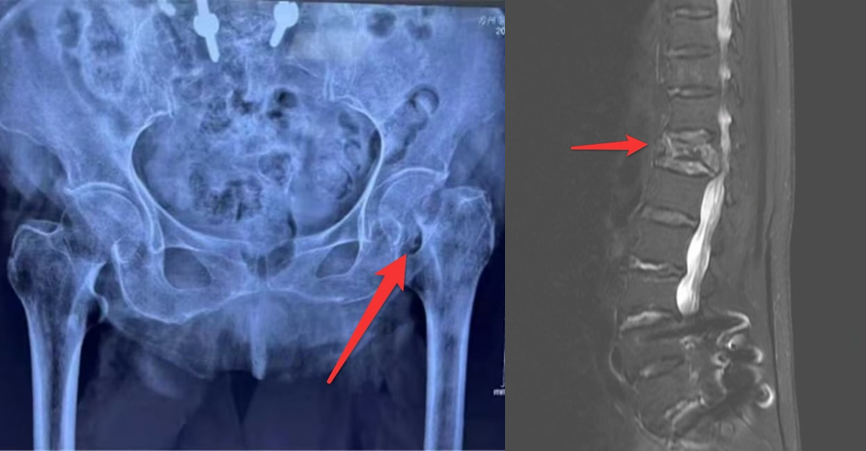

家属怀抱最后一线希望来到苏大附四院骨科。骨科姜为民主任了解患者情况及家属诉求后,为患者进行全面检查与详细评估。入院检查发现,老人除髋部问题外,还存在腰部损伤——影像检查显示第12胸椎骨折,同时伴有高热、腹泻等症状,体温最高达39.4℃,血钾和血糖指标波动剧烈。

术后,钱老太太各项生命指标平稳,无需转入ICU监护。在骨科张霞芬护士长带领的护理团队精心照料下,患者恢复良好。术后第六日,按治疗计划行第二次脊椎骨折手术——在局部麻醉下,刘义杰、陈唐亦衡两位医师协助姜主任,仅用20分钟便顺利完成T12椎体强化术。术后次日,老人即可坐起,肺部情况较术前明显改善,不久便康复出院。